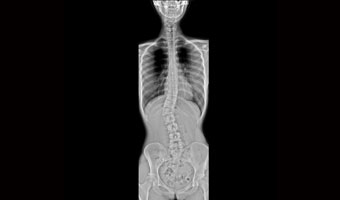

Yenilikçi tam çerçeve görüntüleme platformuyla Yeni Oriental 1000L serisi panorama DR, tek pozlamayla kolayca tam omurga görüntüleme elde eder ve donatılmış "Tele-Eye" sistemi, gerçek zamanlı odalar arası gözleme ve FOV’un hassas şekilde ayarlanmasına olanak tanır. Sistem, tam otomatik akıllı rafla birlikte, doğru tanıyı kolaylaştıracak temassız ve hızlı bir inceleme sürecini de beraberinde getiriyor.

Bir pozlama

Tek çekimde tüm uzuv, tüm omurganın görüntülenmesi, düşük dozda hızlı inceleme, daha fazla hasta bakımı sağlar.

MIX akıllı dengeli görüntüleme sistemi

Çok seviyeli filtreleme teknolojisini, çok ölçekli görüntü ayrıştırma algoritmasını ve görüntü birleştirme algoritmasını birleştirerek vücut kısmı sınırlamasını kırar, kafatası, boyun, göğüs, karın vb. gibi farklı vücut parçalarının tek bir düşük dozda, tekdüze ve görüntülenmesine olanak tanır. tutarlı HD görüntüler.

Tek çekimde tam omurga ve alt ekstremite görüntüleme.

Ergen skolyozu ve geleneksel göğüs röntgeni taraması.